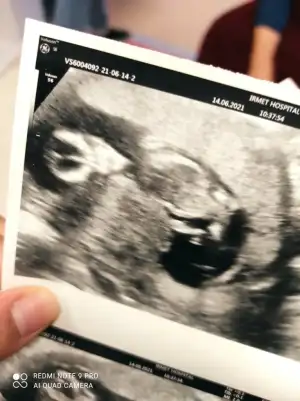

Merhaba erkek demiştin doktor bugün tahmin yaptı erkege benziyor dedi ☺️iki hafta sonra net söyler herhalde değişmezse doğru bildiniz buda 12+3 görüntülerimiz

• IMG_20210614_104639.webp

IMG_20210614_104639.webp

27,6 KB · Görüntüleme: 27

• IMG_20210614_104635.webp

IMG_20210614_104635.webp

32,7 KB · Görüntüleme: 27

• IMG_20210614_104628.webp

IMG_20210614_104628.webp

35,4 KB · Görüntüleme: 26